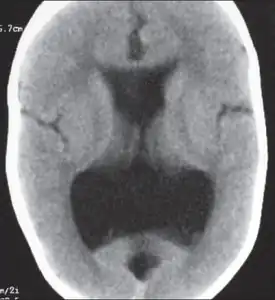

Colpocephaly is characterized by disproportionately large occipital horns of the lateral ventricles (also frontal and temporal ventricles in some cases). MRI and CT scans of patients demonstrate abnormally thick gray matter with thin poorly myelinated white matter. This happens as a result of partial or complete absence of the corpus callosum. Corpus callosum is the band of white matter connecting the two cerebral hemispheres. The corpus callosum plays an extremely important role in interhemispheric communication, thus lack of or absence of these neural fibers results in a number of disabilities.[12]

The lemon sign on CT scans of patients refers to the shape of the fetal skull when the frontal bones lose their normal convex contour and appear flattened or inwardly scalloped. This gives the skull a shape similar to that of a lemon. The sign is seen on transverse sonograms of the fetal cranium obtained at the level of the ventricles. A special case is found in literature where lissencephaly, colpocephaly, and septal agenesis are all present together. The CT scans of the patient shows the ventricular system having a unique appearance of a crown of a king. This is referred to as the 'CROWN SIGN'.[8]

After birth, MR imaging can be done to look for cephalic abnormalities. This is the most commonly used method for diagnosing colpocephaly. Physicians look for abnormally large occipital horns of the lateral ventricles and diminished thickness of white matter.[12] Spinal tapping is not a preferred method for diagnosis because newborn babies with colpocephaly or hydrocephaly have open fontanelles which makes it difficult to collect CSF. Also, colpocephaly is not associated with increased pressure.[13]